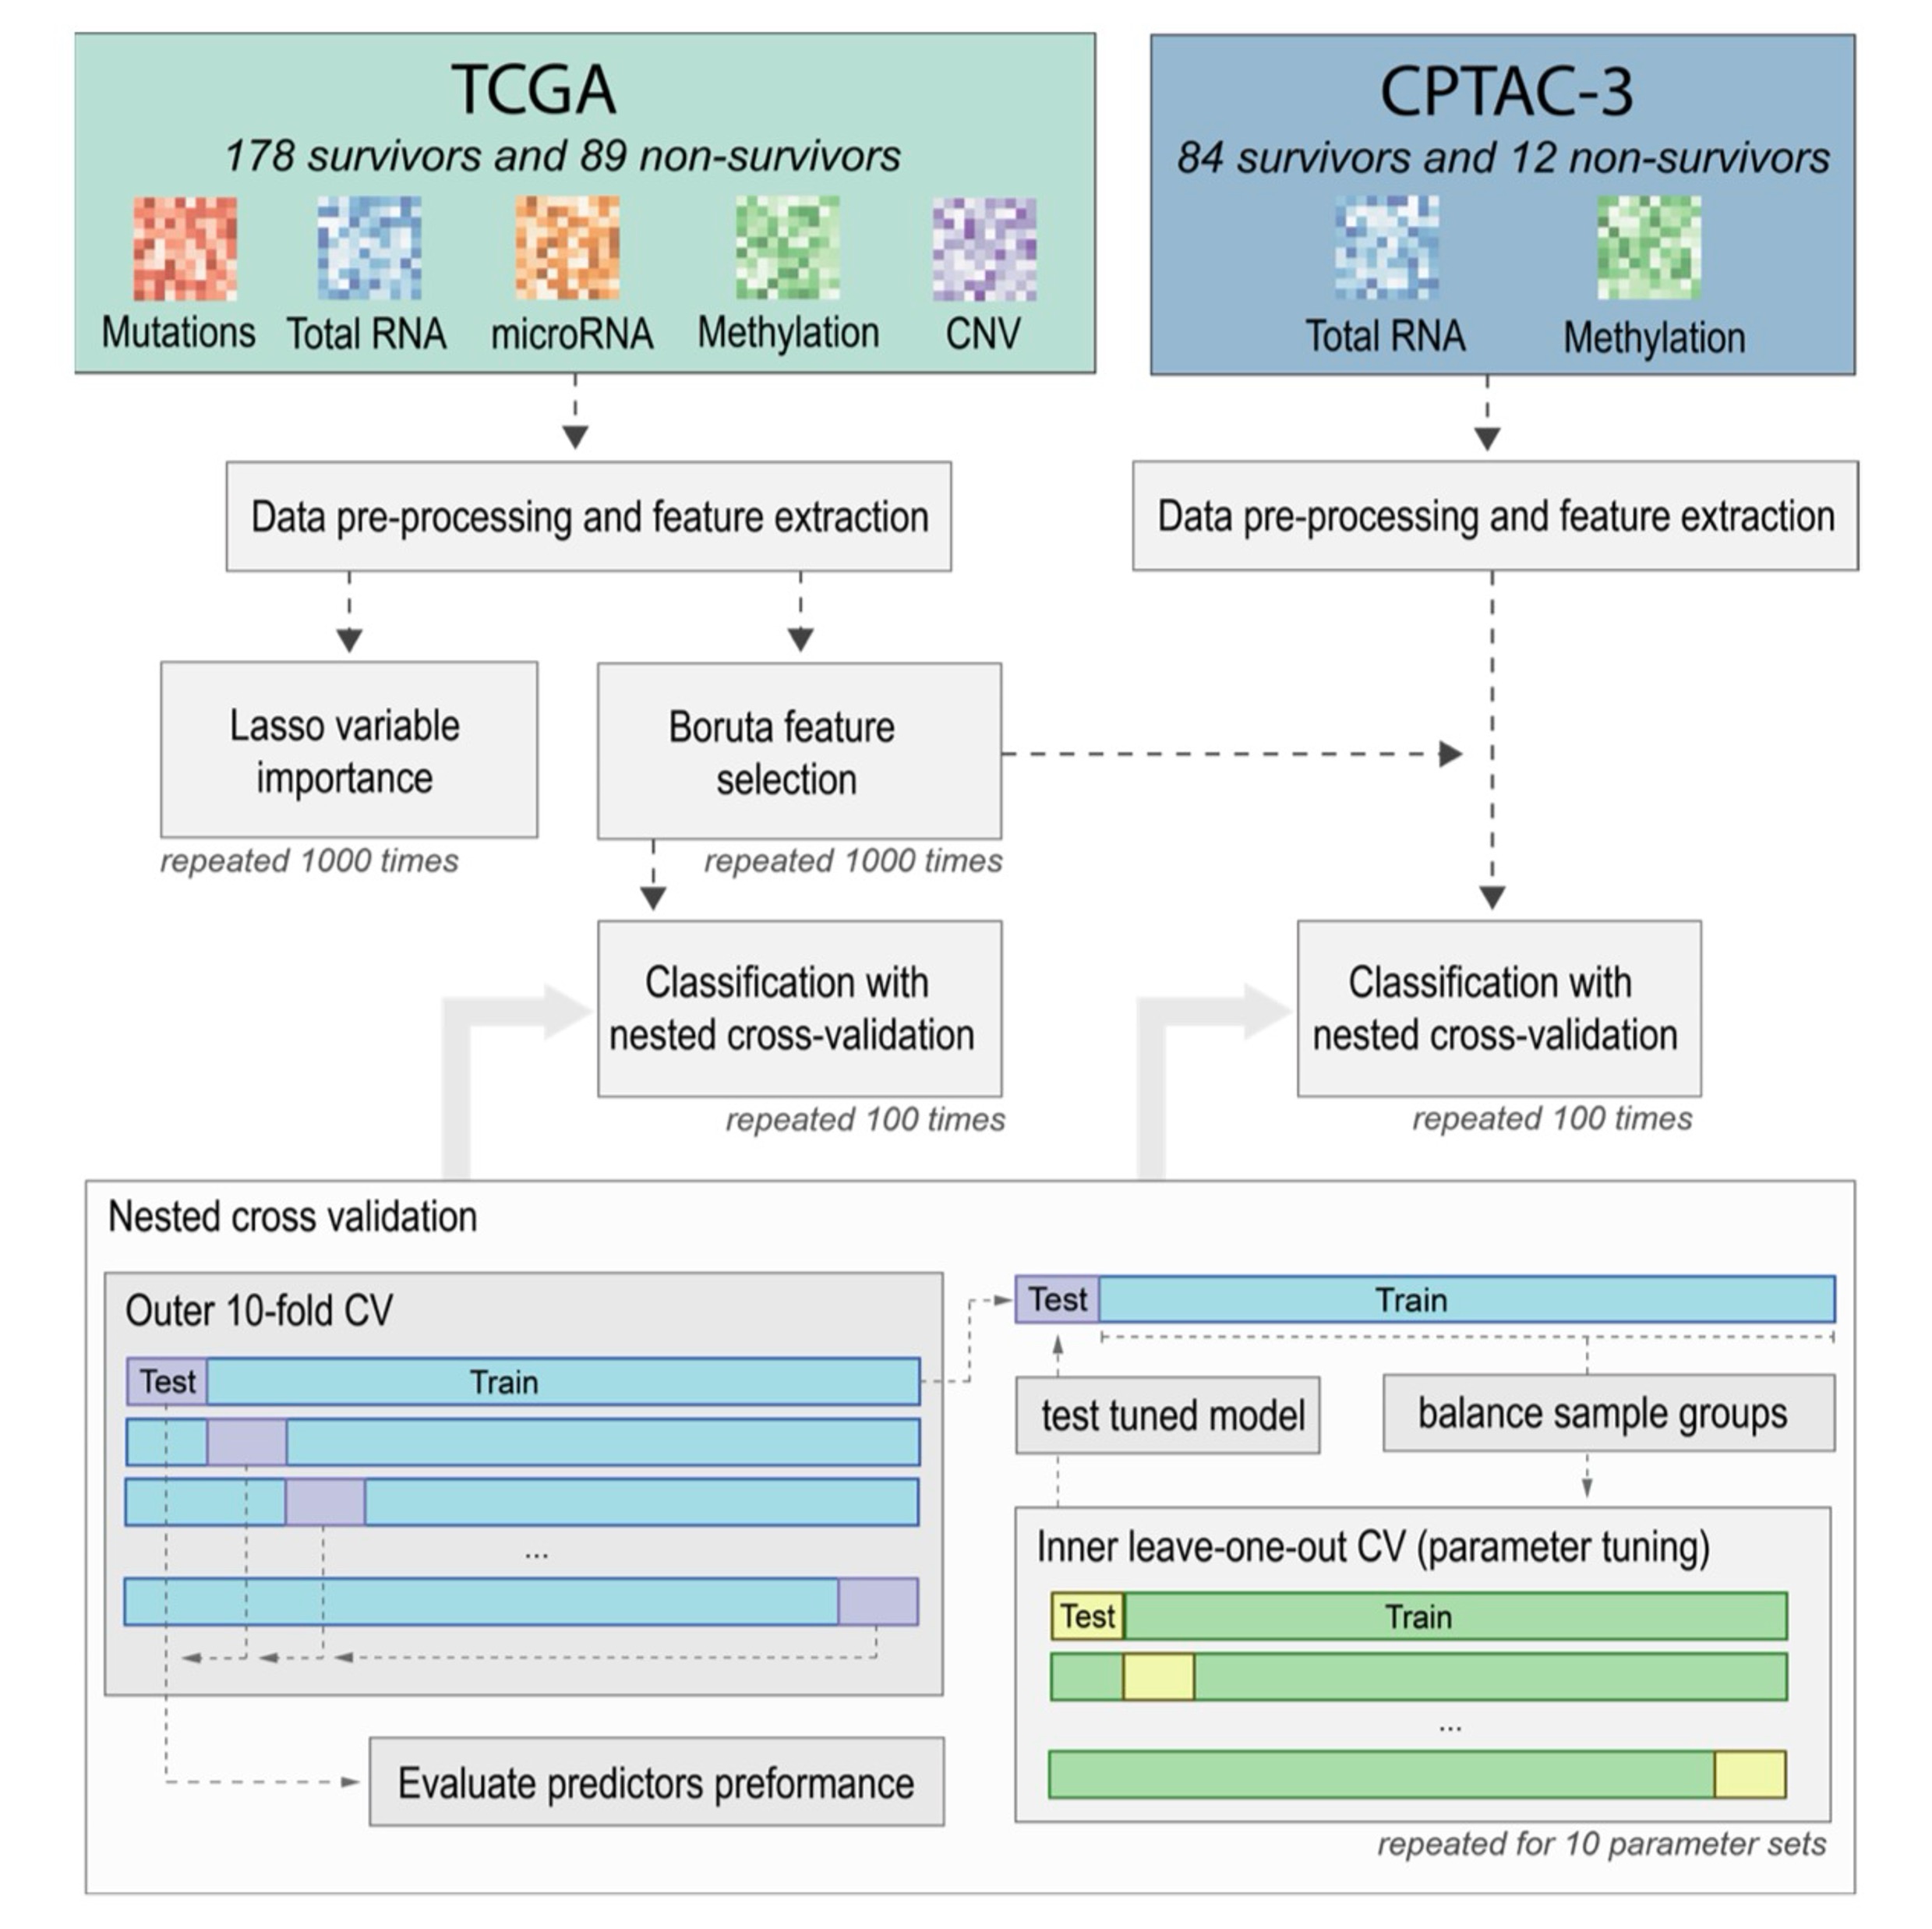

Multiomics-based feature extraction and selection for the prediction of lung cancer survivalRoman Jaksik, Kamila Szumała, Khanh N. Dinh, and Jarosław ŚmiejaInternational Journal of Molecular Sciences, 2024

Multiomics-based feature extraction and selection for the prediction of lung cancer survivalRoman Jaksik, Kamila Szumała, Khanh N. Dinh, and Jarosław ŚmiejaInternational Journal of Molecular Sciences, 2024Lung cancer is a global health challenge, hindered by delayed diagnosis and the disease’s complex molecular landscape. Accurate patient survival prediction is critical, motivating the exploration of various -omics datasets using machine learning methods. Leveraging multi-omics data, this study seeks to enhance the accuracy of survival prediction by proposing new feature extraction techniques combined with unbiased feature selection. Two lung adenocarcinoma multi-omics datasets, originating from the TCGA and CPTAC-3 projects, were employed for this purpose, emphasizing gene expression, methylation, and mutations as the most relevant data sources that provide features for the survival prediction models. Additionally, gene set aggregation was shown to be the most effective feature extraction method for mutation and copy number variation data. Using the TCGA dataset, we identified 32 molecular features that allowed the construction of a 2-year survival prediction model with an AUC of 0.839. The selected features were additionally tested on an independent CPTAC-3 dataset, achieving an AUC of 0.815 in nested cross-validation, which confirmed the robustness of the identified features.

@article{jaksik2024multiomics, dimensions = {true}, title = {Multiomics-based feature extraction and selection for the prediction of lung cancer survival}, author = {Jaksik, Roman and Szuma{\l}a, Kamila and Dinh, Khanh N. and {\'S}mieja, Jaros{\l}aw}, journal = {International Journal of Molecular Sciences}, volume = {25}, number = {7}, pages = {3661}, year = {2024}, publisher = {MDPI}, doi = {10.3390/ijms25073661}, } -